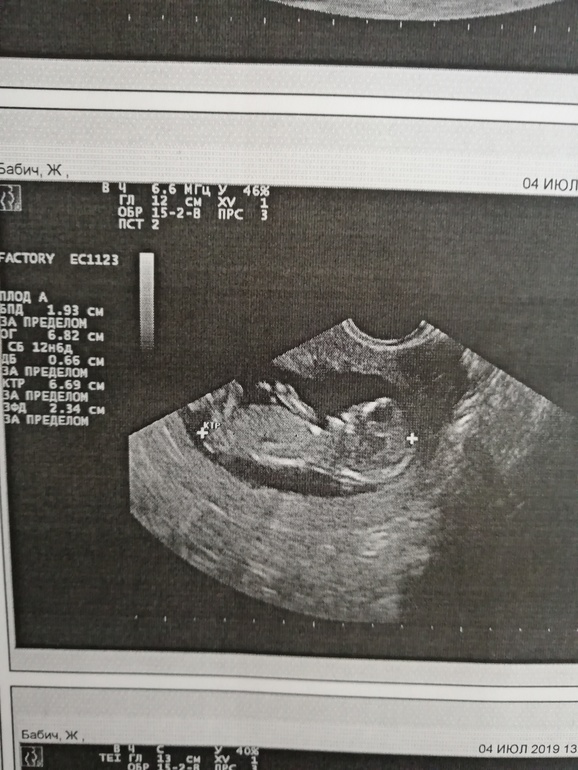

Добрый вечер мамуськи) сделала и я сегодня долгожданный 1 скрининг. Ура)) 12 нед. и 5 дней. ПДР 11 января 2020г. Вес 55 г. Женщина которая делала УЗИ, мне не очень понравилась, слова не вытянишь. Я как и многие тут не понимаю снимки, точнее не вижу кто, мальчик или девочка)) Но знаю точно, что в группе есть девочки которые понимают. Помогите понять пожалуйста)) кого вы видите.

По 1му фото предположу пацана. Но не факт. На остальных вообще ниче не видно.

Спасибо большое! 🤗 И Вас поздравляю)) Ой, она сказала, что похоже на мальчика, но там пуповина, может и нет. Блин, а так интерессно))

На фото к сожалению не видно бугорка. Поздравляю с удачным скринингом. А кровь скоро будет готова? Сколько делают. У нас через неделю скрининг.

К сожалению полового бугорка не видно (